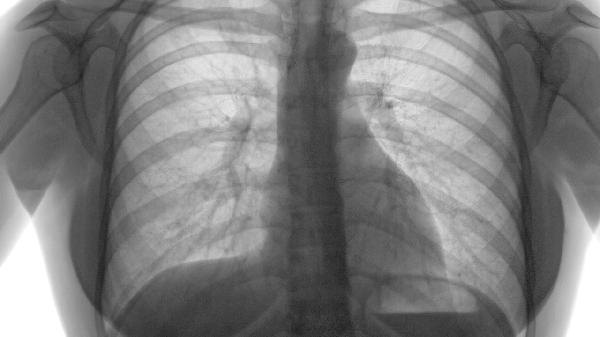

肺气肿导致肺泡结构破坏,气体交换效率降低,血氧饱和度下降引发慢性缺氧。缺氧刺激肾脏分泌促红细胞生成素,血液黏稠度增加加重循环负担。治疗需通过长期低流量吸氧1-2L/min纠正缺氧,配合支气管扩张剂如沙丁胺醇气雾剂、噻托溴铵粉雾剂改善通气。

肺泡毛细血管床减少使肺血管阻力升高,右心室后负荷持续增加可发展为肺心病。超声心动图可检测肺动脉收缩压,治疗采用磷酸二酯酶-5抑制剂西地那非、内皮素受体拮抗剂波生坦或钙通道阻滞剂硝苯地平降低肺动脉压力。